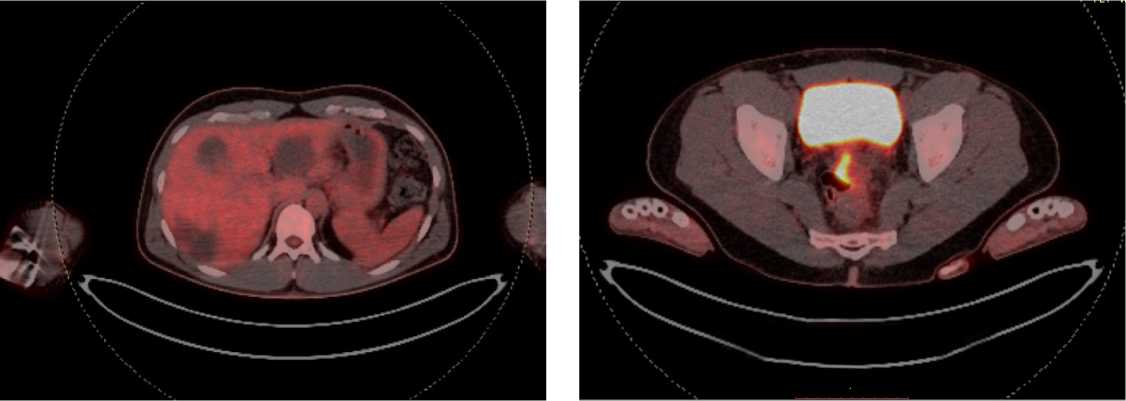

Для оценки метаболической активности остаточной опухолевой ткани выполнено позитронно-эмиссионная томография, совмещенная с компьютерной томографией (ПЭТ-КТ) в марте 2022 г., по результатам которого выявлено умеренное повышение уровня метаболической активности в проекции выходного отдела желудка и двух ЛУ брюшной полости, без значимой динамики в сравнении с предшествующим исследованием.

С целью оценки метаболической активности метастазов и первичной опухоли пациенту выполнено ПЭТ/КТ всего тела с 18-ФДГ: патологическая активность стенки среднеампулярного отдела прямой кишки 38,4 × 13,3 мм, SUV max 13,50 (рис. 13).

Рис. 13. Результаты позитронно-эмиссионной томографии с 18-ФДГ на фоне иммунотерапии пембролизумабом у пациента 38 лет с диагнозом метастатический колоректальный рак с признаками микросателлитной нестабильности; патологическая активность стенки среднеампулярного отдела прямой кишки 38,4 × 13,3 мм, SUV max 13,50 (март 2024 г.)

Fig. 13. Results of positron emission tomography with 18-FDG during immunotherapy with pembrolizumab in a 38-year-old patient diagnosed with metastatic MSI-H colorectal cancer; pathological activity of the wall of the mid-ampullary part of the rectum 38.4 × 13.3 mm, SUV max 13.50 (March 2024)